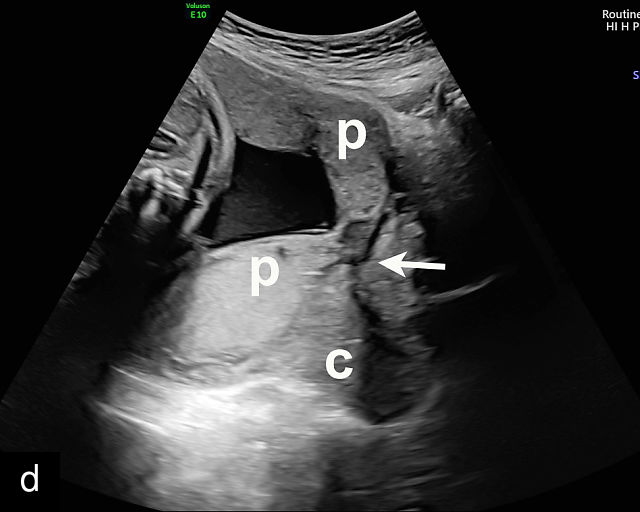

In the past, placenta previa was classified as complete, partial, marginal or low-lying.50,61 However, with advancements in ultrasound technology allowing precise assessment of the relationship between the placenta and the internal cervical os, the classification has been simplified.67 Placenta previa now refers to cases in which the placenta overlies the internal os to any degree, while low-lying placenta describes cases in which the lower placental edge lies within 2 cm of the internal os (Figure 5).51,66,67

5

Placenta previa and low-lying placenta. (a) Transabdominal grayscale ultrasound image suspicious for placenta previa. The placenta (PL) appears to overlie the internal cervical os (CX). Note the time stamp: 2:19:37. (b) Transvaginal ultrasound of the same patient taken approximately 50 minutes later. Note the time stamp: 3:10:25. The internal os and the lower placental edge are both clearly seen, and the placenta does not overlie the internal os. Because the lower placental edge is 1.93 cm from the internal os, it will likely resolve by the third trimester. (c) Transabdominal grayscale ultrasound of placenta previa. The placenta (p) covers the cervix, but the cervix, especially the internal os, cannot be visualized due to shadowing. (d) Transabdominal grayscale ultrasound of placenta previa. The placenta (p) covers the cervix (c) but shadowing obscures adequate visualization. The internal os is indicated by the arrow. (e) False-positive image of placenta previa on transabdominal grayscale ultrasound. The bladder (b) is full, pushing the anterior and posterior walls of the lower uterine segment (ls) together making it appear that the placenta (p) overlies the internal os of the cervix. In reality, the line depicted by the arrowheads is where the anterior and posterior walls of the lower segment are in proximity to each other. The cervix is much lower and is obscured by shadowing (c). (f) Transabdominal grayscale ultrasound image of placenta previa. The placenta (p) covers the cervix (c), but the cervix, especially the internal os, cannot be visualized due to shadowing. b, bladder. (g) Transvaginal grayscale ultrasound image of placenta previa. The placenta (p) completely covers the internal os (arrow) of the cervix (c). The internal os can be seen clearly. h, fetal head. (h) Transvaginal grayscale ultrasound image of posterior low-lying placenta (p). The lower placental edge is clearly seen and is 1.56 cm from the internal os (arrow) of the cervix (c). The placental edge and the internal os are clearly seen. h, fetal head. (i) Transvaginal grayscale ultrasound image of a posterior placenta previa (p). The internal cervical os is clearly seen (arrow). c, cervix. (j) Transvaginal grayscale ultrasound image of an anterior placenta previa (p). The internal cervical os is clearly seen (arrow). c, cervix; h, fetal head. (k) Transvaginal grayscale ultrasound image of a posterior placenta that was thought to be low-lying on transabdominal sonography but could not be adequately assessed. This examination clearly shows the lower edge of the placenta (p) to be 2.18 cm from the internal os (arrow) of the cervix, firmly establishing that the placenta is not low-lying and allowing the patient to undergo labor safely and deliver vaginally. c, cervix. (l) Transvaginal grayscale ultrasound image of placenta previa. The placenta (p) completely covers the internal os (arrow) of the cervix (c). The internal os can be seen clearly.

Most cases of placenta previa will be suspected prenatally by transabdominal ultrasound.49 However, this approach has several limitations and may be inaccurate.72,73,74 because the relationship between the placenta and the internal cervical os may be difficult to assess by transabdominal ultrasound.72,73,74 The bladder may be full, pushing the anterior and posterior walls of the lower uterine segment together, falsely creating the impression of a placenta previa (Figure 5e).61 There may be considerable shadowing, including by the fetal presenting part, which may limit the accuracy of transabdominal ultrasound (Figure 5d,f).75 Posterior placentas may be more difficult to assess.

Transvaginal ultrasound overcomes these limitations (Figure 5g–l).72,73,74,76 The probe is inserted into the vagina and therefore is closer to the region of interest.51,61 In addition, transvaginal transducers have higher frequencies and superior resolution compared to transabdominal transducers. Transvaginal ultrasound is safe and is not associated with increased bleeding.72,73,74,75,76 As such, transvaginal ultrasound should be the imaging modality of choice whenever there is suspicion of placenta previa.49,67,77